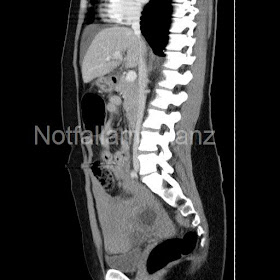

Die perforierte EU ist eine der wenigen gynäkologischen Notfälle, die akut lebensbedohlich sind. Bei der Patientin ließ die Anamnese mit fehlendem sexuellen Kontakt (in den letzten Wochen) und die weiterhin bestehende Menstruation ließen zunächst die Möglichkeit einer Magenperforation zu. Das plötzliche Einsetzen epigastrischer Beschwerden mit dem Bild eines akuten Abdomens, ließ den Chirurgen zunächst in diese Richtung denken. Das gynäkologische Konsil war primär nicht richtungsweisend. Erst die Konstellation aus CT und erhöhtem HCG ließen eine gynäkologische Genese wieder in den Vordergrund rücken.